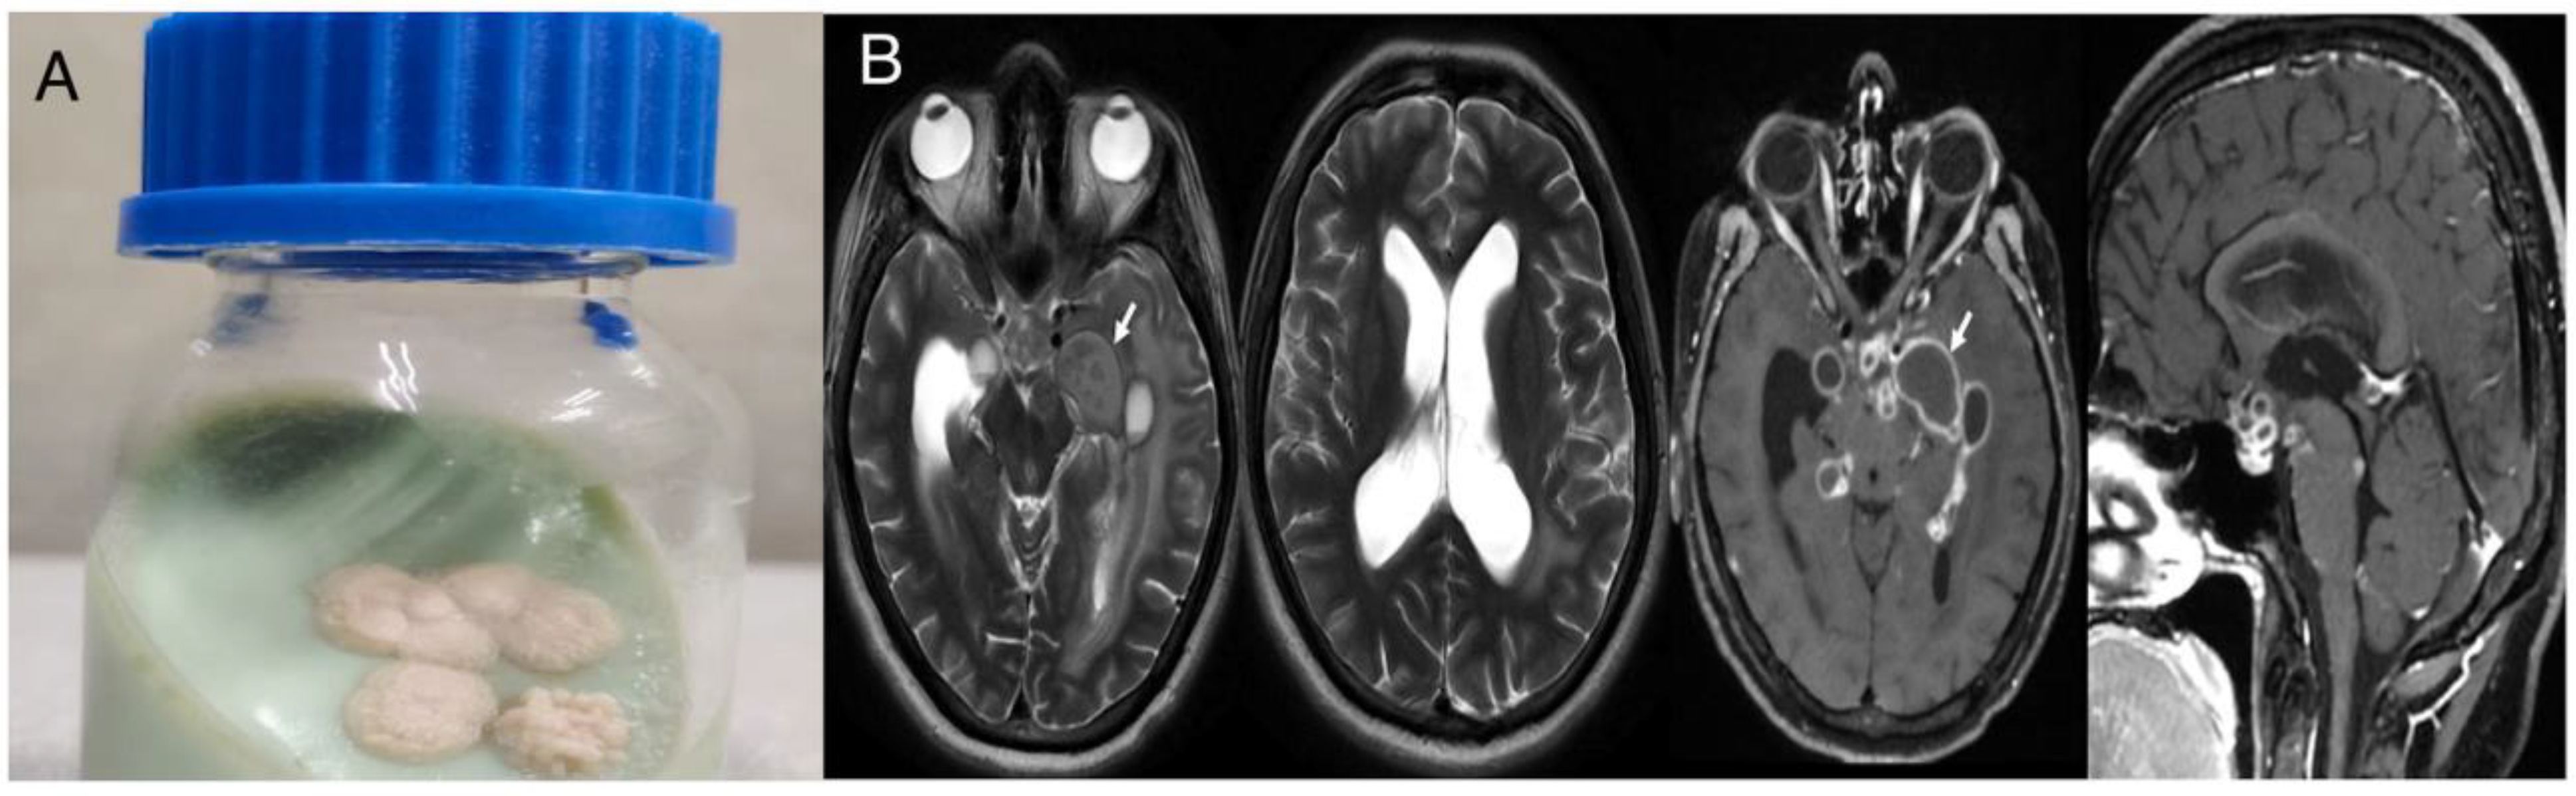

Case 1

Case 2

Case 3

Case 4